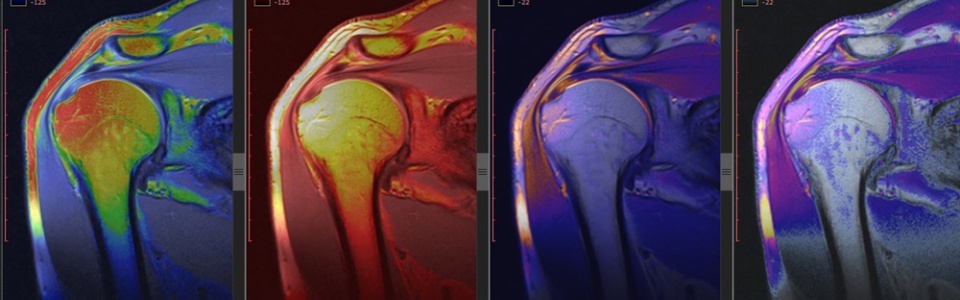

SLAP損傷は、肩関節関節唇の上方部分の怪我です。SLAPという単語は、上方関節唇(Superior Labrum ) の前方から後方にかけて(Anterior to Superior )の損傷を略したものです。これは肩関節傷害で非常によく見られる診断です。SLAP損傷には、重症度や治療ストラテジーが異なる多くの様々なバリエーションがあります。過去において、外科医はすべてのSLAP損傷を手術したがりましたが、私たちは手術なしでもうまくいくものもあることを学びました。事実、いくらかのSLAP損傷は心配する必要さえないのです。